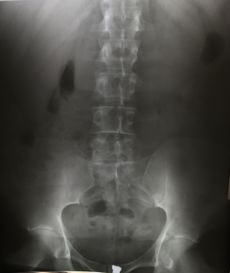

التصوير الشعاعي إنگليزية: Radiography: وهو يستخدم الأشعة السينية لرؤية الأجزاء غير المرئية أو صعبة التصوير. الهدف الأساسي من الأشعة السينية المستخدمة في التشخيص هو تصوير داخل الجسم، وبشكل خاص العظام والتي يمكن رؤيتها بدقة مثلى (128 تدرج للون الرمادي).

Projectional radiography